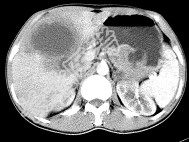

- 单项选择题女,61岁, 上腹部疼痛1个月,食欲减退, 消瘦,CT所见如图, 最可能的诊断为( )

A、原发性肝癌

B、肝包虫病

C、肝转移瘤

D、胃癌肝转移

E、肝脓肿